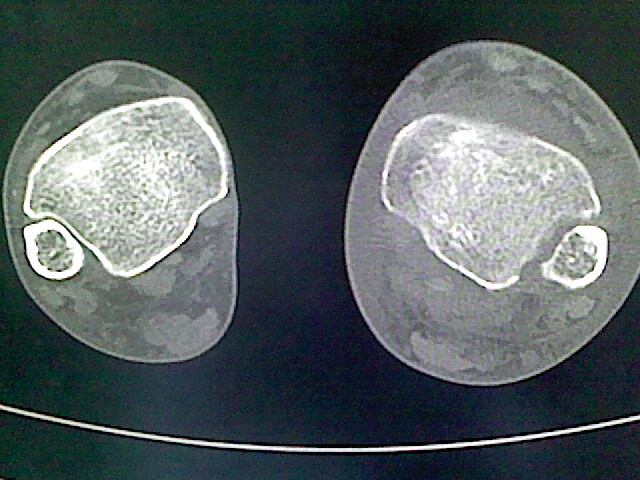

男,76岁,左小腿疼痛,不能站立

骨病经验少看不好,退行性骨关节病的改变是有,但软组织广泛肿胀又不是骨感染来的、又不是肿瘤破坏来的、又不是代谢病来的、又不是外伤所致......有脉管病吗?

本例骨质改变主要表现为滑膜或韧带区的骨侵蚀融解(胫腓联合区骨质破坏无硬化边),距骨后部骨质破坏区有硬化边及死骨样改变.所以,本例考虑关节结核可能性大,绒毛膜结节性滑膜炎多发于中年,且极少见于膝髋以外的关节,骨质硬坏也以压陷吸收为主,有明显的硬化边,骨膜增生呈结节状(可以mr鉴别),所以本例暂除外.

另不除外可引起相似表现的其他炎症如布氏杆菌性关节炎等